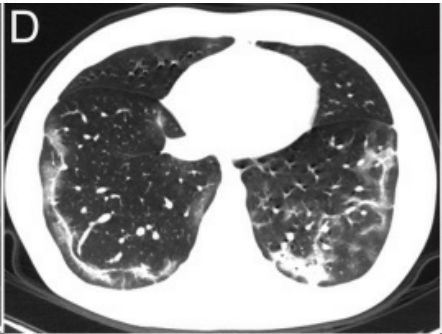

▎病灶分布

病灶主要分布在胸膜下,与胸膜几乎平行,是这次新冠肺炎最具特色的影像学表现。

片状磨玻璃阴影,以胸膜下分布为主。注意,病灶与胸膜大约平行。

图20

线条状病灶,以胸膜下分布为主。

图21

结节状病灶,也是以胸膜下分布为主。

图22

总之,不管什么病灶,都是以胸膜下分布为主。

图23